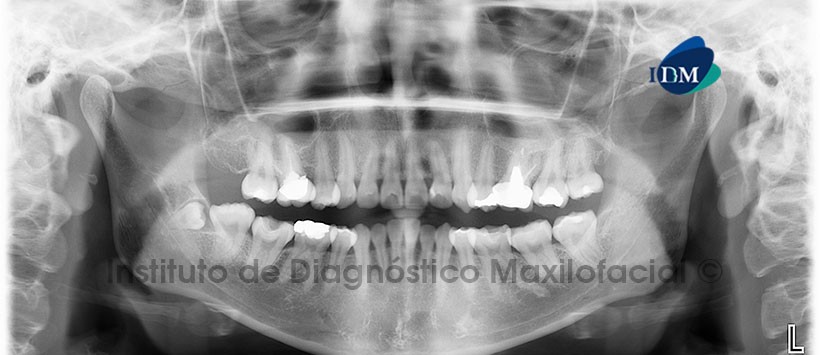

A la evaluación de la radiografía panorámica se aprecia la presencia de un diente supernumerario en evolución intraósea y en posición. Además se aprecia ausencia de primeras premolares y de la pieza 18, la pieza 38 extruída y en posición distoangular. Alteración en la anatomia y morfologia dentaria de piezas anterosuperiores compatible con dientes en forma de pala (Figura 1).